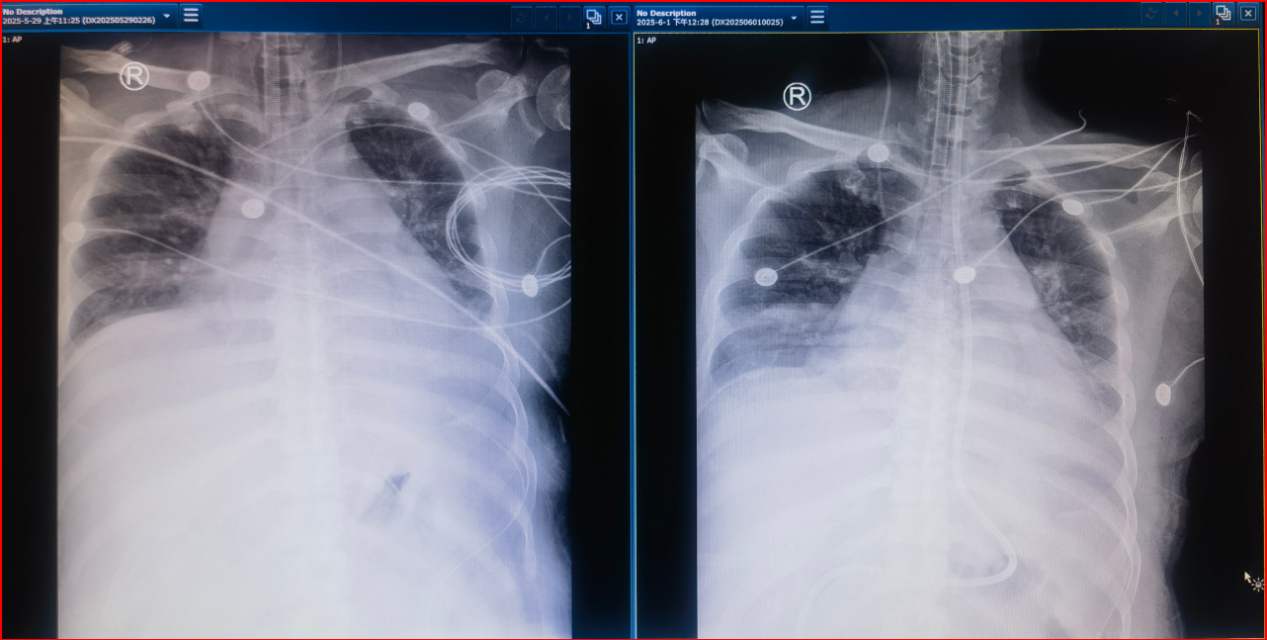

图4 影像学检查结果(5月21日)

图8 影像学检查结果(5月26日)

图15 影像学检查结果(左:5月29日;右:6月1日)